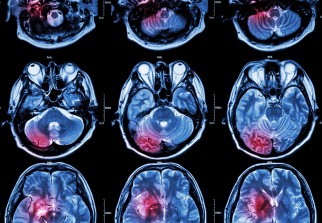

Si l'on a globalement une idée de ce que signifient accident vasculaire cérébral (AVC) et rupture d'anévrisme, la différence entre les deux est plutôt floue. En vérité, la rupture d'anévrisme est un cas particulier d'AVC. On vous explique.

On confond souvent rupture d'anévrisme cérébral et accident vasculaire cérébral, ou AVC. Si ces deux affections touchent la circulation sanguine du cerveau et constituent une urgence vitale, elles n'ont pas tout à fait la même définition.

En réalité, l'accident vasculaire cérébral est une dénomination globale, qui inclue plusieurs affections, dont la rupture d'anévrisme.

L'accident vasculaire cérébral est une défaillance de la circulation sanguine dans une région plus ou moins grande du cerveau. Dans la zone touchée, les cellules sont privées d'oxygène apporté par le sang, et risquent donc de mourir si ce manque dure trop longtemps.

L'AVC regroupe plusieurs affections qui ont différentes origines. Dans un premier temps, deux grandes classes d'AVC se distinguent.

L'AVC peut être dû à un arrêt du flux sanguin, à cause d'un caillot par exemple. On parle alors d'AVC ischémique cérébral, aussi appelé infarctus cérébral. Ce type d'AVC concerne 80% des cas d'AVC. Le caillot qui bouche le vaisseau peut avoir été amené par la circulation sanguine (AVC embolique), ou s'être formé directement dans le cerveau (thrombose).

Ce type d'AVC s'oppose à l'AVC hémorragique, causé par la rupture d'un vaisseau sanguin à l'intérieur du cerveau, entraînant une hémorragie. Un hématome se forme, comprime la zone cérébrale atteinte et interrompt la circulation sanguine. Ce scénario concerne 20% des AVC.

Parmi les AVC hémorragiques, on distingue deux cas particuliers : la malformation des vaisseaux sanguins et la rupture d'anévrisme. La malformation des vaisseaux sanguins, présente généralement dès la naissance, augmente le risque d'AVC hémorragique.

L'anévrisme cérébral est un point faible d'un vaisseau sanguin, une dilatation anormale d'une artère qui irrigue le cerveau. Ce type d'anomalie est plus souvent présent chez les personnes souffrant d'hypertension, de cholestérol ou encore chez les fumeurs. Sous la pression artérielle, un ballon de sang se forme au niveau de l'anévrisme. La rupture de l'anévrisme entraîne alors une hémorragie cérébrale qui peut être fatale. Ce cas particulier concerne 10% des AVC et est responsable de 50% des AVC mortels chez les personnes de moins de 45 ans.